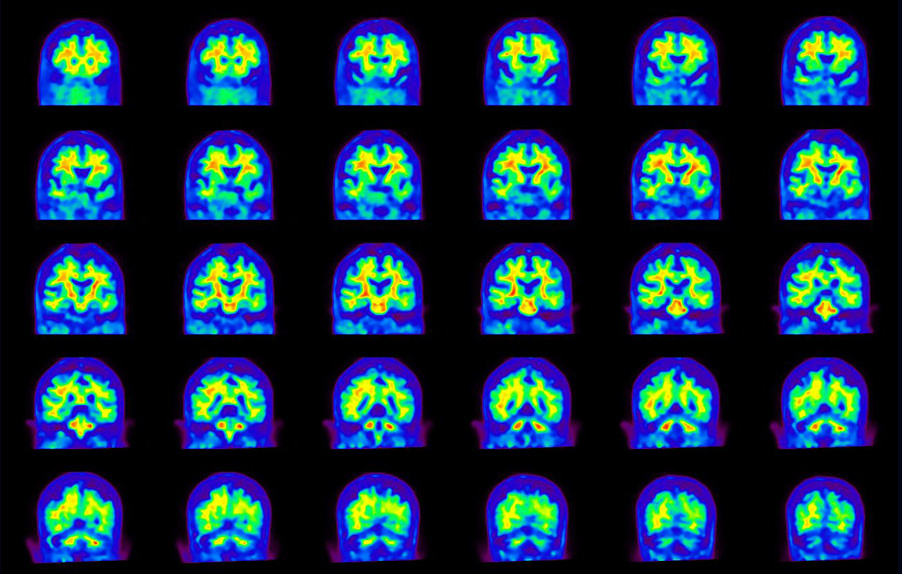

Coronal